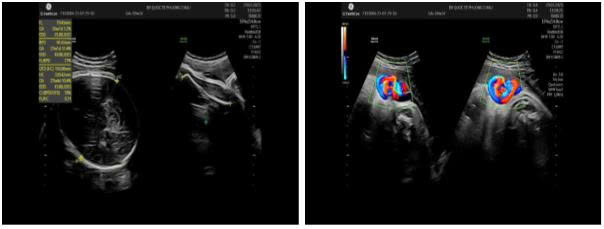

Mang thai lần đầu, chị V.T.H (32 tuổi) luôn tự nhủ phải khám thai đúng và đủ để đảm bảo an toàn cho con. Nhờ tuân thủ lịch khám định kỳ tại Bệnh viện Quốc tế Phương Châu, chị đã phát hiện được điều bất thường quan trọng ở tuần 32: thai nhi có nút thắt dây rốn.

Dây rốn thắt nút

- Siêu âm Doppler, theo dõi tim thai - cơn gò bằng monitor liên tục

Tại đây, khi đặt monitor, bác sĩ ghi nhận tim thai bất thường, có dấu hiệu đe doạ thai nhi. Quyết định mổ lấy thai được đưa ra nhanh chóng - một quyết định thể hiện kinh nghiệm và sự nhạy bén của đội ngũ điều trị.